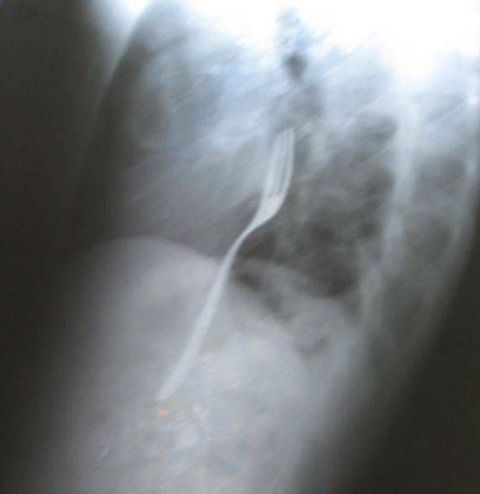

Romeno engole garfo inteiro em aposta

Um homem de 25 anos bebeu e apostou com um amigo que conseguiria engolir um garfo inteiro, em Baca, na Romênia. O romeno foi ao médico reclamando de dor, segundo declarou ao jornal Libertatea, e ao tirar um raio-X, teve o garfo preso a garganta revelado.

De acordo com o jornal, os médicos do paciente esperam que o garfo saia de forma natural. O homem declarou que, caso o garfo chegue ao seu estômago e cause ferimentos a ele, haverá a necessidade de cirurgia.